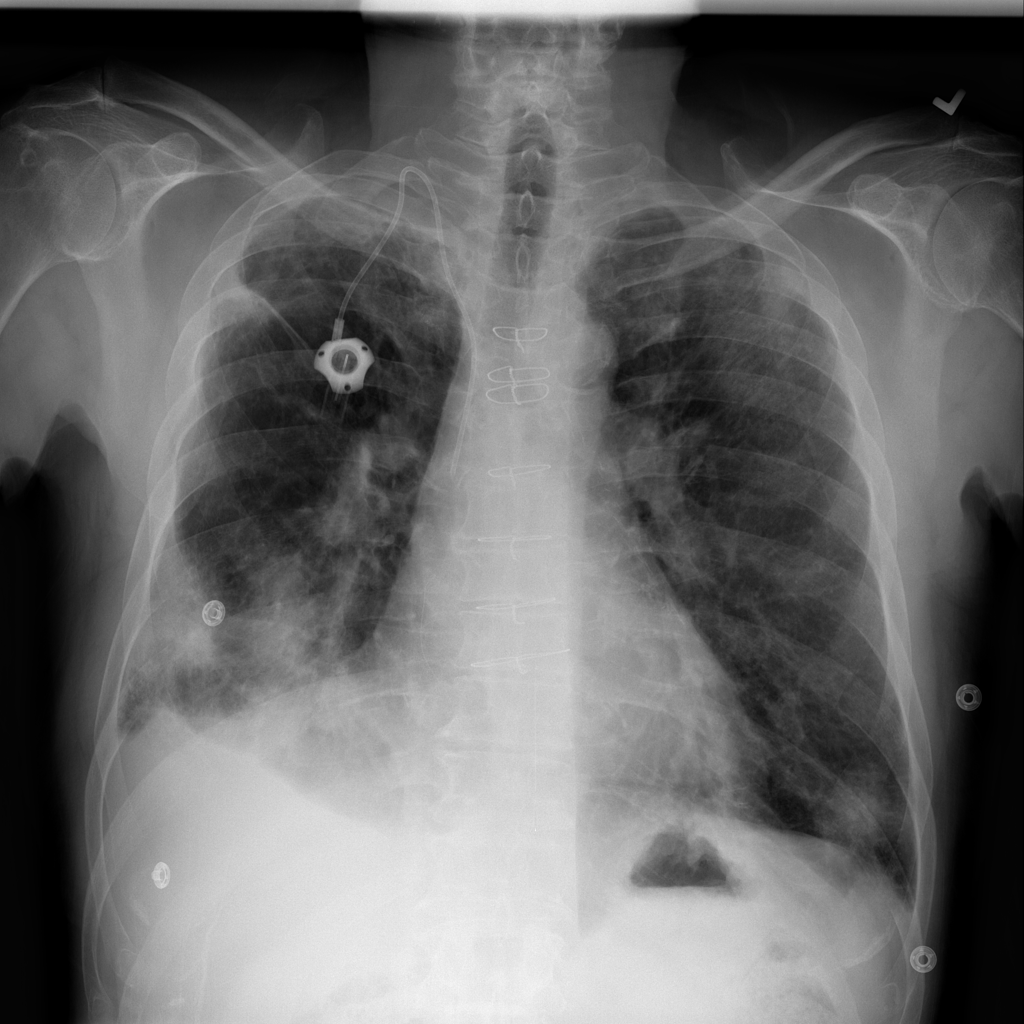

PAT-E81B · IMG-000Effusion

PAT-E81B · IMG-000

PA